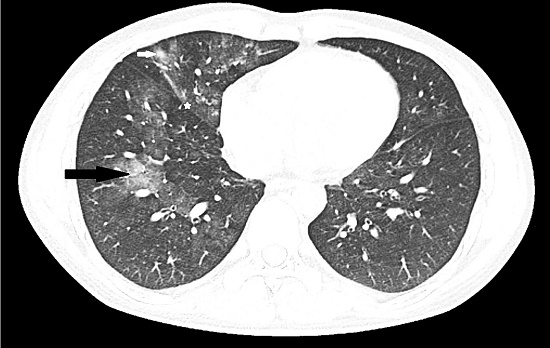

Laboratory investigations revealed hemoglobin 9.6 gm%, hematocrit 29%, and blood counts within normal limits without any increase in eosinophils. Serum biochemical testing showed renal and liver functions and electrolytes to be within normal limits, as were the urinalysis results. Random blood glucose was 140 mg/dL, and ESR was 12 mm/ hour. Chest X-ray showed increased interstitial markings. Further, high-resolution CT-thorax revealed ground-glass opacities in the right middle lobe (anterior to the fissure—white arrow) and right lower lobe (posterior to the fissure--black arrow) consistent with DAH (Figure 1).

Images of the right upper lobe were not included as there was no abnormality in the upper lobes. Bronchoscopy performed after 4 days of admission was normal, and Broncho-alveolar lavage (BAL) cytology showed normal alveolar macrophages. BAL bacterial, viral, fungal, AFB, and Pneumocystis jirovecii cultures were negative. Echocardiogram showed normal left ventricular function (ejection fraction: 65%), without valvular abnormalities. Ultrasonography (upper abdomen) was normal. The coagulation profile was normal. Serology for HIV, hepatitis B, and C viruses was non-reactive. Work-up for autoimmune disorders and vasculitis consisting of antinuclear antibody, rheumatoid factor, antineutrophilic cytoplasmic antibodies, serum complement factors (C3 and C4), cryoglobulin and angiotensin-converting enzyme levels were normal. Urine toxicological screen (lateral flow chromatographic competitive binding immunoassay; SRL Diagnostics Ltd., Mumbai, India), performed in view of the cannabis abuse history, was positive for cannabinoids (threshold: 50 ng/mL).